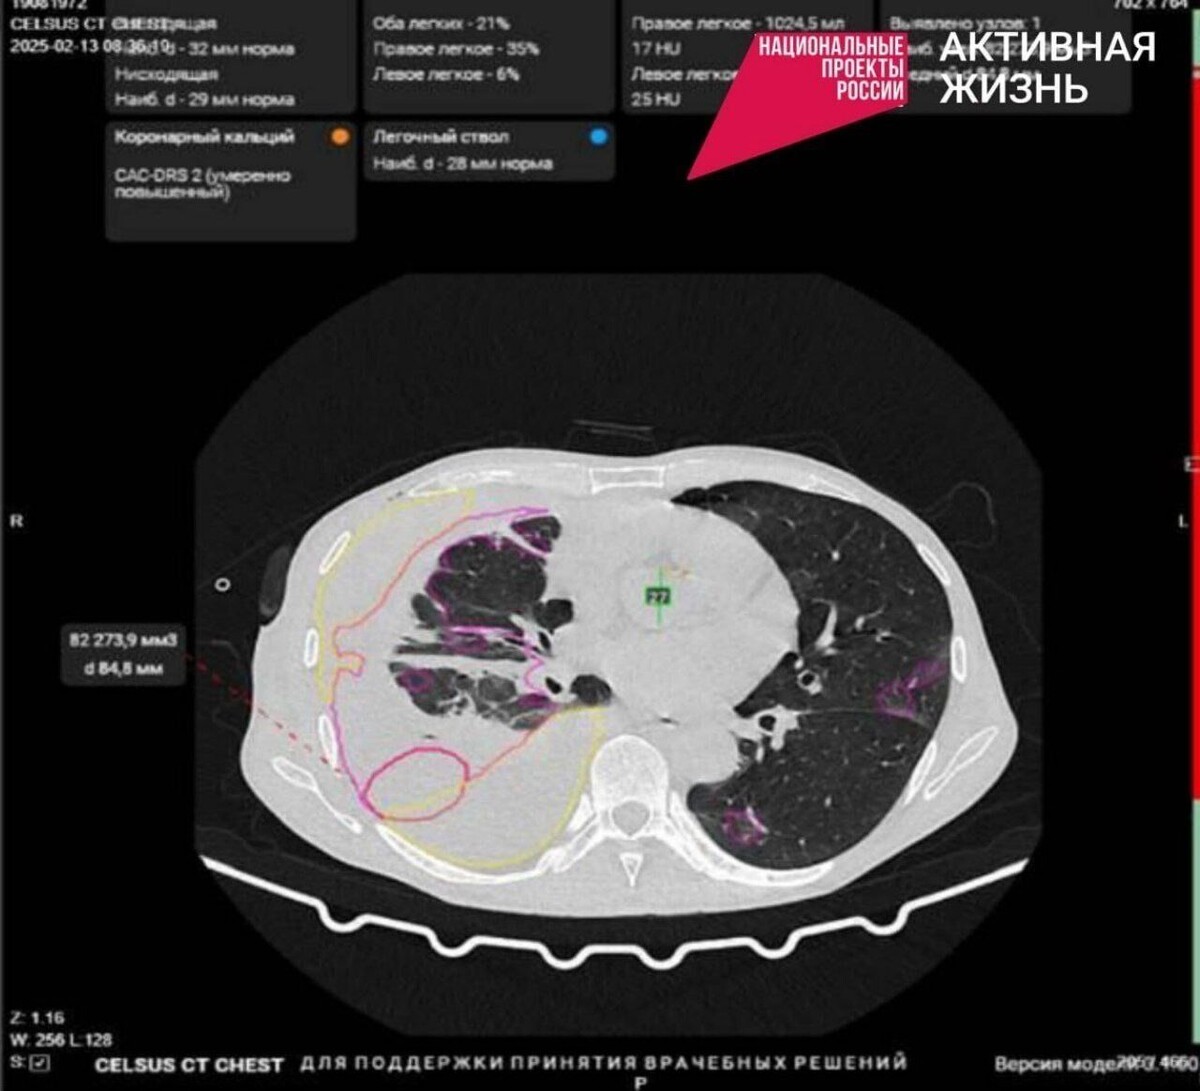

Искусственный интеллект теперь помогает находить признаки патологий на медицинских изображениях (рентгенограммы, маммограммы, КТ), а также делает необходимые рентгенологу измерения. В том числе ИИ сможет диагностировать злокачественные опухоли на ранней стадии.

В здравоохранении Белгородской области впервые начали использовать нейросети. «Первооткрывателем» стала Борисовская ЦРБ, где произошло комплексное обновление цифрового оборудования лучевой диагностики.